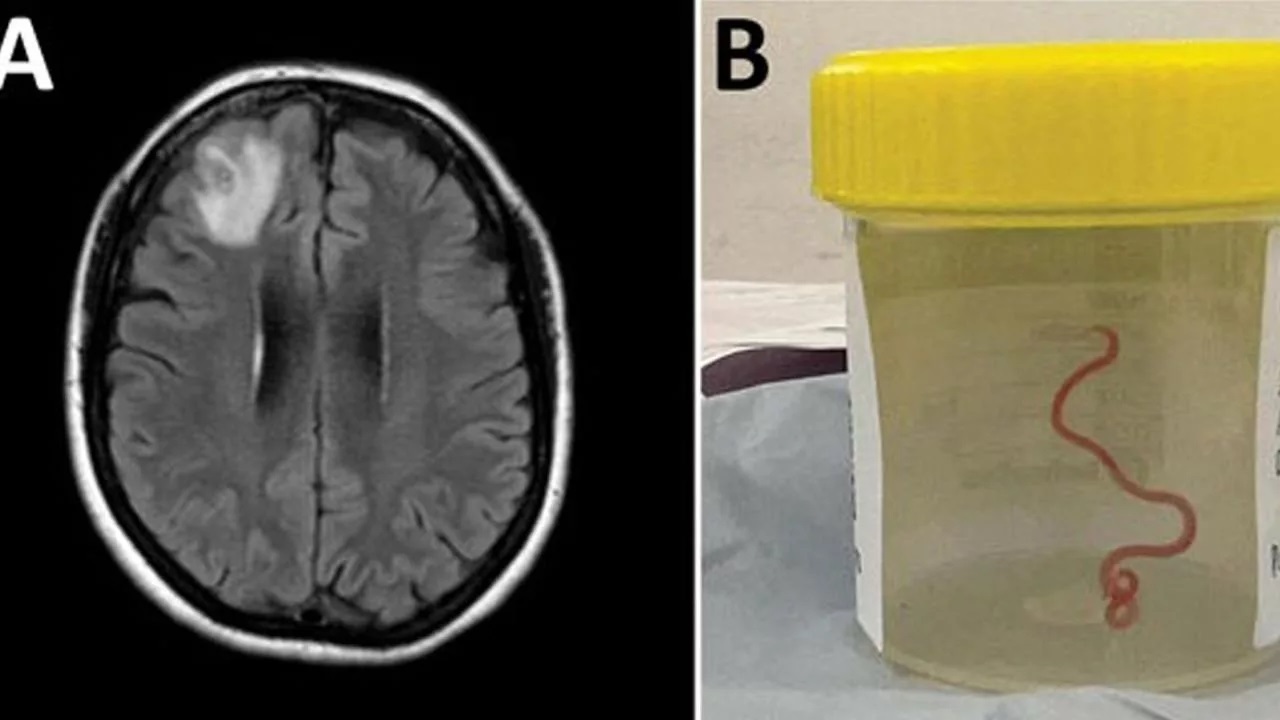

در سال ۲۰۲۲ برای یک بازه زمانی سهماهه، فرد دچار مشکل فراموشی و افزایش شدت افسردگی میشود. پزشکان در این مقطع زمانی از او MRI میگیرند که یک ضایعه در لوب پیشانی را نشان میدهد.

در این منطقه از مغز فرد، یک کرم لولهای ۸ سانتیمتری پیدا و خارج میشود. این کرم درون مغز این زن استرالیایی زنده بوده است. پس از برداشتن کرم، فرد تحت درمان قرار میگیرد تا لاروهای احتمالی از بین بروند. لاروهای این کرم میتوانند تا ۴ سال در بدن حیوانات زنده بماند.